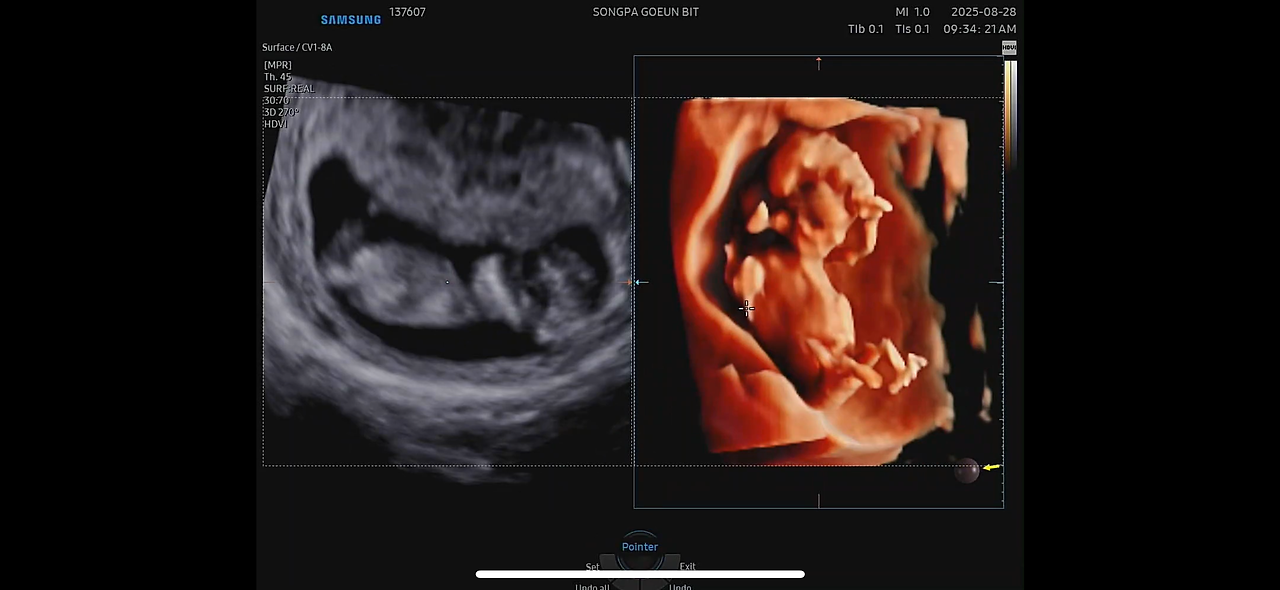

예약해 둔 정밀 초음파는 정확한 시간에 시작되었다.

7분 남짓의 시간 동안, 내 손바닥보다 작은 생명이 화면 속에서 움직이고 있었다.

불과 12cm 남짓한 몸인데, 손과 발, 머리, 엉덩이까지 모두 자리 잡고 있었다.

입체 초음파 화면 속 아이는 작은 손을 머리 위로 올리고 있었다.

선생님은 “손을 머리에 얹고 있네요.”라고 설명했지만,

내 눈에는 마치 ‘경례’를 하는 모습처럼 보였다.

KakaoTalk_20251010_124426389.png

12주 정밀초음파

12주 정밀초음파 동영상